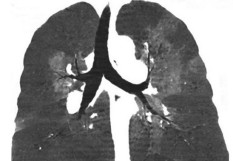

Embolie pulmonaire : des recommandations pour une prise en charge ambulatoire

[LES GRANDS CONGRES DE L'ANNEE] Dans le cadre de notre série consacrée aux grands congrès médicaux de l'année scolaire qui vient de s’achever, nous revenons sur les 29es Journées européennes de la Société française de cardiologie, organisées à Paris du 16 au 19 janvier 2019. Elles ont fait le tour de la spécialité et ont détaillé les évolutions de prise en charge des cardiopathies. Une session organisée conjointement avec la Société française de médecine vasculaire a notamment permis de détailler de nouvelles recommandations de traitement dans l’embolie pulmonaire et certaines thromboses veineuses. On peut, en effet, désormais traiter en ville ou après une hospitalisation de moins de 48 heures les malades avec une embolie pulmonaire de faible risque. "En 2010, 95 % des embolies pulmonaires (EP)étaient hospitalisées, avec une durée moyenne de séjour de 10 jours", a rappelé le Pr Nicolas Meneveau, cardiologue au CHRU de Besançon. "Depuis quelques années, se pose cependant la question d’une prise en charge ambulatoire de cette affection, un nombre croissant de patients avec une EP étant identifiés grâce à la diffusion de l’angioscanner multi-barrettes, dont beaucoup n’auraient pas été traités auparavant. Ils ont au bout du compte un état de santé plutôt satisfaisant". Par ailleurs, "le traitement de l’EP s’est simplifié avec l’emploi du fondaparinux, des anticoagulants directs, et on dispose d’outils performants comme les scores Pesi (pour Pulmonary Embolism Severity Index) ou Pesi simplifié (à respectivement 11 et 6 variables), et le score Hestia (à 11 questions), pour identifier avec une bonne valeur prédictive négative les patients à faible risque pouvant bénéficier d’une telle stratégie thérapeutique". Enfin, les études de registre et méta-analyses révèlent que le repos au lit n’est pas forcément nécessaire en cas d’EP à bas risque et, surtout, qu’un traitement au domicile ou après une hospitalisation de moins de 48 heures, peut être très sûr chez des patients bien sélectionnés. Une revue de la littérature publiée en 2017, par le Pr Pierre-Marie Roy (CHU d’Angers), à partir de 3 méta-analyses et de 23 études ayant impliqué 3671 patients avec une EP, traités le plus souvent à domicile, a ainsi conclu à un taux de complications entre 1 et 3 mois (hémorragies majeures, récidives thrombo-emboliques) inférieur à 2 %, et à un pourcentage de décès de moins de 3 % (Roy PM, et al. Thromb Res. 2017;155:92-100). La Société européenne de cardiologie (ESC) en 2014 et l’American College of Chest Physicians (ACCP) en 2016, ont admis ce nouveau mode de traitement des EP à faible risque avec un niveau de recommandation proche (IIaB pour l’ESC).   Des conditions médicales et sociales Pour que le choix d’une prise en charge ambulatoire soit fait, il faudra cependant non seulement que les risques médicaux soient estimés faibles au vu des scores (fréquence cardiaque, SaO2, absence de comorbidité sévère, de risque hémorragique …), "mais aussi que le patient puisse avoir facilement accès aux soins en cas de problème, qu’il soit motivé, et ait un environnement psycho-social adapté", a insisté le Pr Meneveau. L’algorithme, proposé par la Société de pneumologie de langue française (SPLF), qui devrait être prochainement publié, conseille de réserver cette prise en charge ambulatoire aux patients avec un score Pesi simplifié ou Hestia égal à 0 (ou Pesi ≤ 85) sans problème thrombo-embolique survenu sous anticoagulant ou suspicion de thrombopénie induite par l’héparine, sans risque hémorragique élevé, insuffisance rénale sévère, comorbidités justifiant une hospitalisation, et  bénéficiant d’un contexte médico-social favorable. "Une autre condition est de faire suivre la consultation d’évaluation initiale, moins de 72 heures après le début de l’EP, d’une consultation à 1 mois puis entre 3 et 6 mois, éventuellement effectuées par le médecin traitant". "La consultation à 1 mois permettra de vérifier la tolérance du traitement anti-coagulant et l’adhésion du patient, avec le respect des éventuels ajustements posologiques, mais aussi d’entreprendre un bilan étiologique, qui impose un examen clinique complet, un dosage du PSA chez l’homme, et une mammographie chez la femme. On vérifiera l’absence de séquelles secondaires à l’EP, lors de la consultation de 3 à 6 mois. Enfin, un suivi annuel sera mis en place". Le Pr Meneveau a souligné "la nécessité de bien organiser le parcours de soins entre ville et hôpital, et avec le médecin traitant".